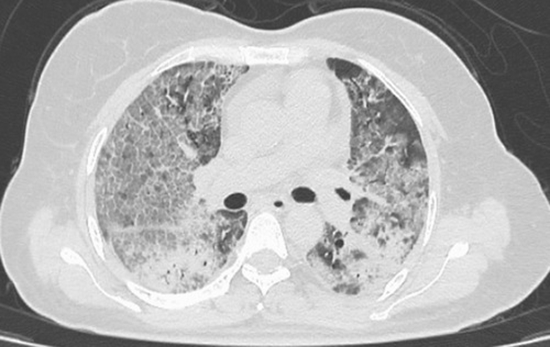

Investigating the relationship between chest CT scan involvement score with vital signs and laboratory findings at the time of referral and the need for hospitalization

According to the proposed model, patients with age over 53 years and oxygen saturation less than 91% and pulmonary index greater than 8 are at a higher risk for unfavorable outcome of hospitalization and this model can predict patients' need for higher level care in the near future. During hospitalization, it should be based on clinical-radiological data at the time of initial consultation